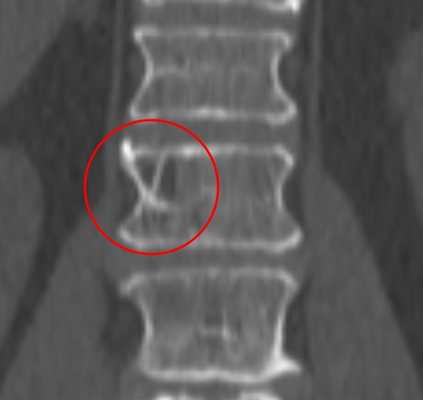

При КТ определяется участок в теле позвонка, в его дуге, ножках или суставных отростках, чаще всего имеющий форму шара или эллипсоида, или неправильную форму. Размеры гемангиомы различные - на томограммах можно можно опухоль начиная от 0,5 см. Редко встречаются гигантские сосудистые образования, занимающие практически весь объем позвонка. Рентгеновская плотность данного участка снижена по сравнению с плотностью губчатого вещества и, тем более, замыкательных пластинок.

На изображении представлен поперечный срез через позвонок. В теле позвонка - типичная гемангиома (H). Цифрой 1 отмечены утолщенные и разреженные трабекулы губчатого вещества, цифрой 2 - периваскулярные пространства, сосудистые лакуны. При компьютерной томографии они имеют низкую плотность, приближающуюся к плотности жира (гемангиолипома).

Типичная гемангиома в грудном позвонке. На аксиальном срезе - справа - отчетливо виден характерный «точечный» «рисунок», обусловленный утолщением трабекул и большим количеством периваскулярного жира.

Небольшая сосудистая опухоль в боковых отделах тела первого поясничного позвонка. При компьютерной томографии выявлен гиподенсный участок плотностью -25…-30 единиц Хаунсфилда, с типичными утолщенными и «разреженными» трабекулами губчатого вещества.

В зависимости от количества периваскулярного жира плотность гемангиомы может колебаться от +200 единиц Хаунсфилда до -40 и меньше, но практически никогда не достигает плотности жировой ткани (-100 единиц Хаунсфилда). В структуре опухоли видны множественные разреженные и утолщенные до 1-3 мм трабекулы, дающие характерный «мелкоточечный» рисунок на аксиальных срезах и «полосатый» рисунок на аксиальных и корональных изображениях. После введения контрастного вещества строма опухоли может усиливаться, зачастую весьма значительно. Наибольшую плотность сосудистые опухоли имеют в артериальную фазу контрастирования. Контраст из сосудистых лакун вымывается быстро, поэтому уже в венозную фазу плотность образования существенно снижается.